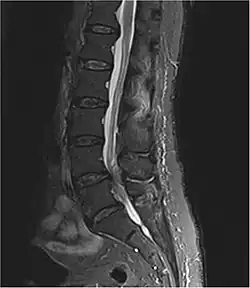

Lumbar spinal stenosis

Lumbar spinal stenosis is classified as a narrowing of the spinal canal in the lumbar region of the vertebrae. This may lead to compression of the nerve root of the spinal cord and result in pain of the lower back and lower extremities. Other symptoms include impaired walking and a slightly stooped posture due to loss of disc height and bulging of the disc. Lumbar spinal stenosis is very prevalent with 9.3% of the general population producing symptoms and the number is continuing to rise in patients older than 60.[16] It's generally an indication for spinal surgery in patients older than 65 years of age.[17] However, there is a myth and fear among most patients that only surgery is the cure for such conditions and spine surgery is very risky. There are many non-surgical treatments available to prevent, halt and even reverse many spine diseases. Also, some surgery patients can be operated on in a daycare procedure or with minimum length of stay in hospital, with statistically good outcomes.[18]

Cauda equina syndrome is a rare syndrome that affects the spinal nerves in the region of the lower back called the cauda equine (Latin for "horses tail"). Injury to the cauda equina can have long lasting ramifications for the individual. Symptoms include lower back pain, bladder disturbances, bowel dysfunction, and anesthesia or paresthesia between the thighs. In order to prevent progressive neurological changes surgery can be a viable option.[21] CT scans, myelograms, and MRIs are used to diagnose cauda equina.[22]